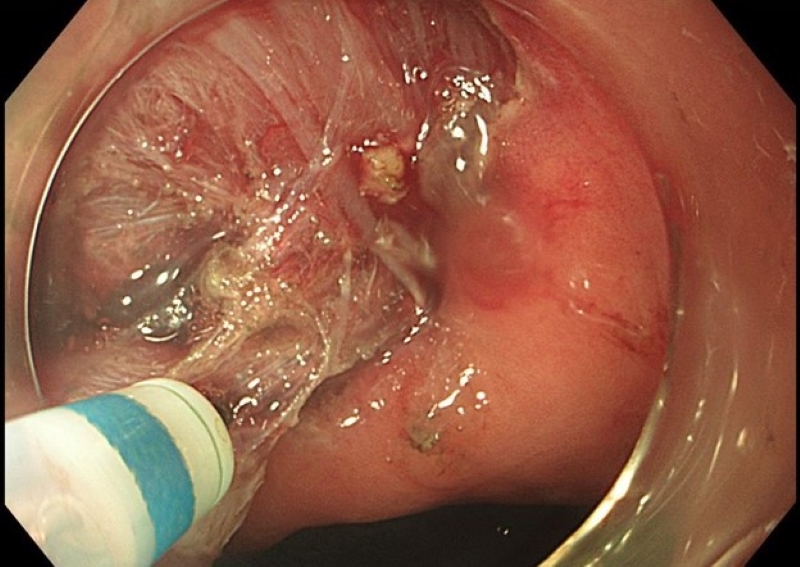

Sau khi hội chẩn chuyên khoa Tiêu hóa, bệnh nhân được chỉ định cắt bỏ u qua nội soi dạ dày bằng kỹ thuật ESSD - phương pháp can thiệp hiện đại, ít xâm lấn, giúp loại bỏ hoàn toàn tổn thương mà không cần phẫu thuật mở.

Khối u được can thiệp qua nội soi dạ dày bằng kỹ thuật ESSD

Quá trình can thiệp được thực hiện bài bản và diễn ra thuận lợi, khối u được lấy trọn vẹn, không ghi nhận biến chứng trong và sau can thiệp. Người bệnh hồi phục nhanh, không đau nhiều, không cần phẫu thuật xâm lấn hay nằm viện kéo dài.